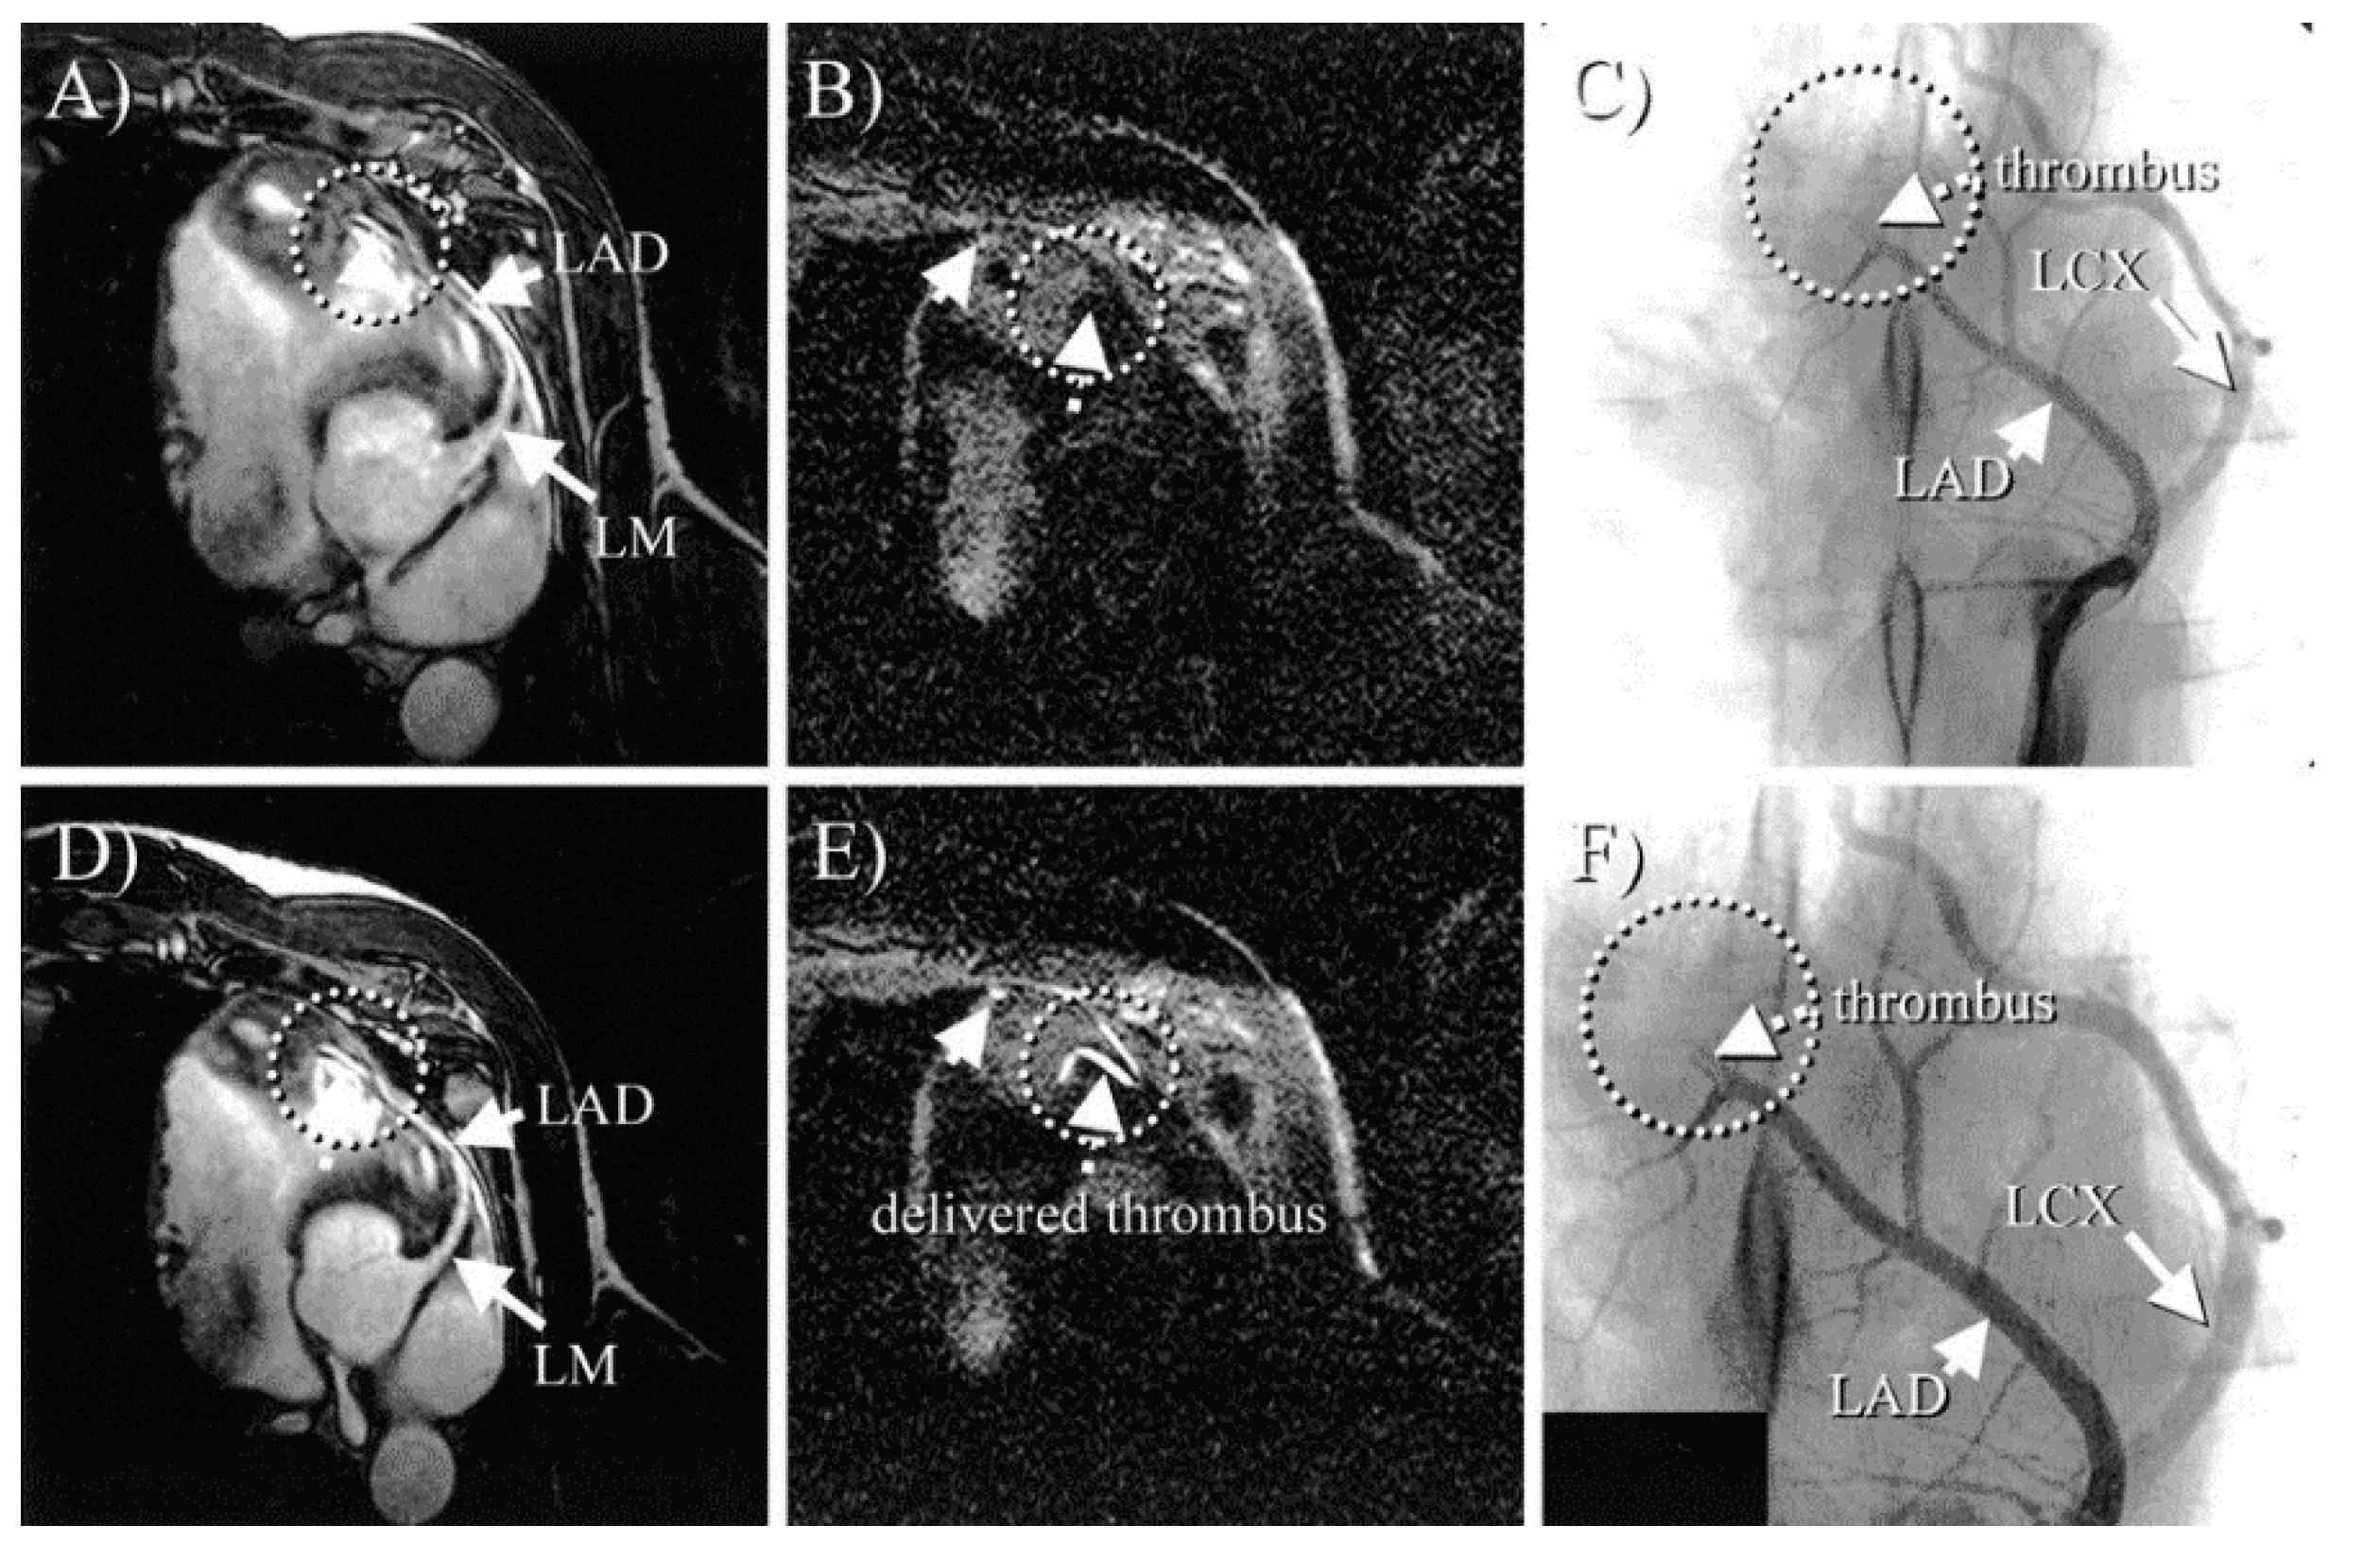

- Botnar, R.M.; Buecker, A.; Wiethoff, A.J.; Parsons, E.C.; Katoh, M.; Katsimaglis, G.; Weisskoff, R.M.; Lauffer, R.B.; Graham, P.B.; Gunther, R.W.; et al. In Vivo Magnetic Resonance Imaging of Coronary Thrombosis Using a Fibrin-Binding Molecular Magnetic Resonance Contrast Agent. Circulation 2004, 110, 1463–1466. [Google Scholar] [CrossRef] [PubMed]

- Spuentrup, E.; Katoh, M.; Buecker, A.; Fausten, B.; Wiethoff, A.J.; Wildberger, J.E.; Haage, P.; Parsons, E.C.; Botnar, R.M.; Graham, P.B.; et al. Molecular MR Imaging of Human Thrombi in a Swine Model of Pulmonary Embolism Using a Fibrin-Specific Contrast Agent. Investig. Radiol. 2007, 42, 586–595. [Google Scholar] [CrossRef]